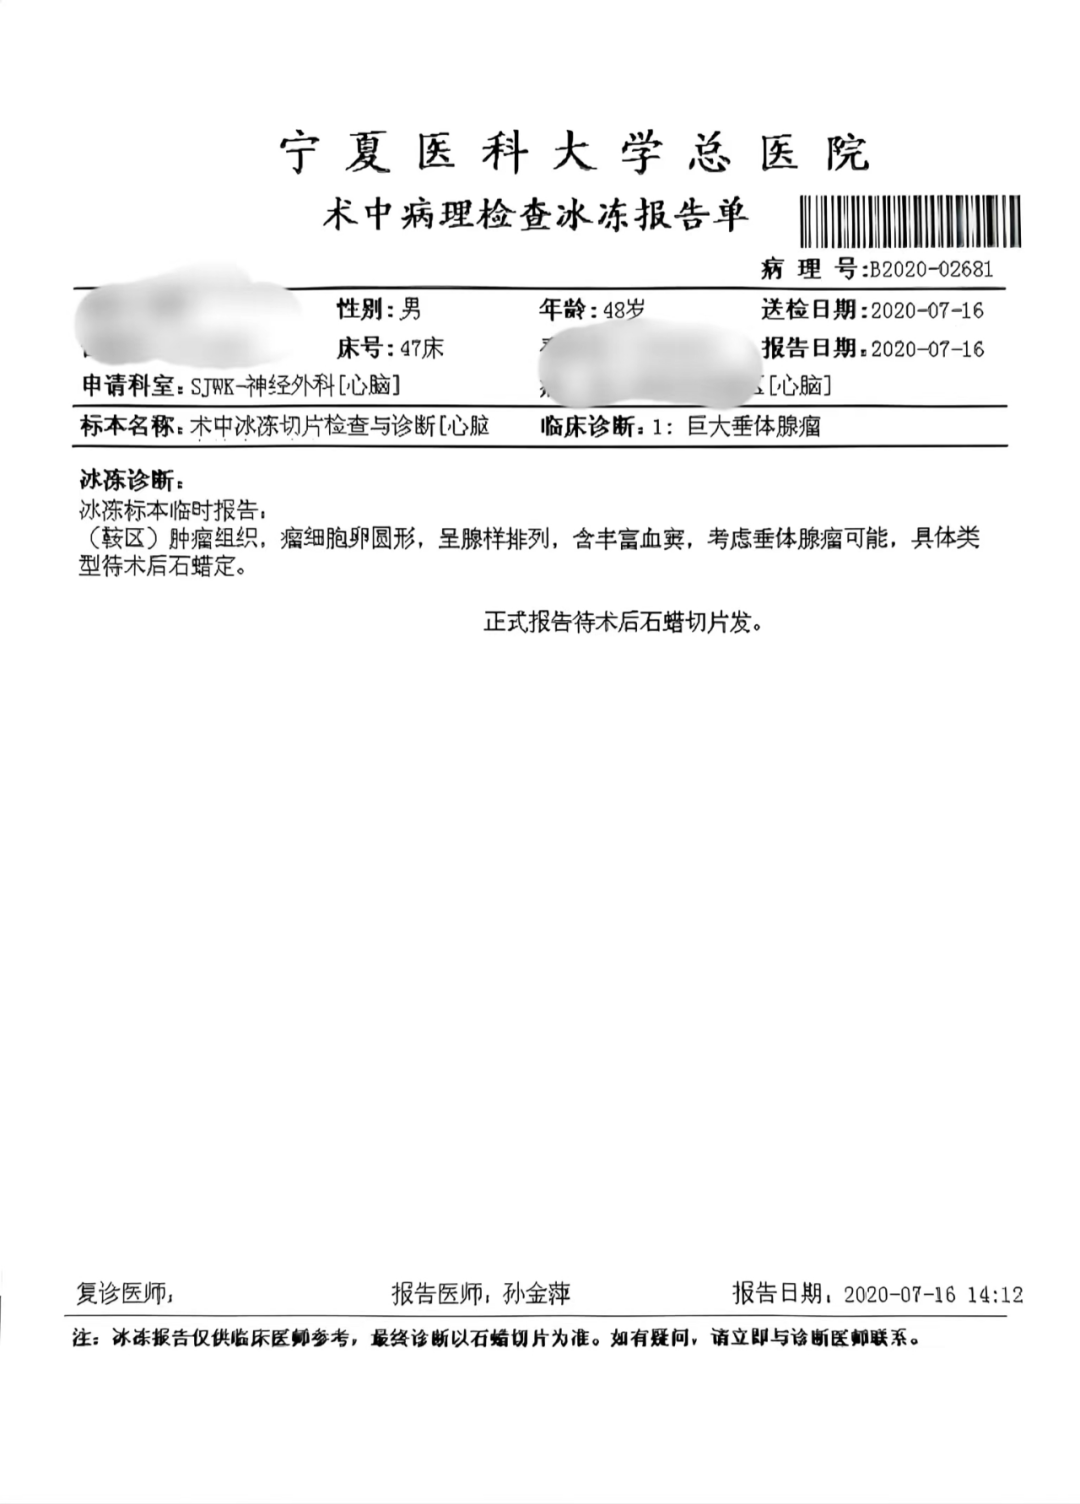

术后冰冻切片标本示:考虑(鞍区)垂体腺瘤